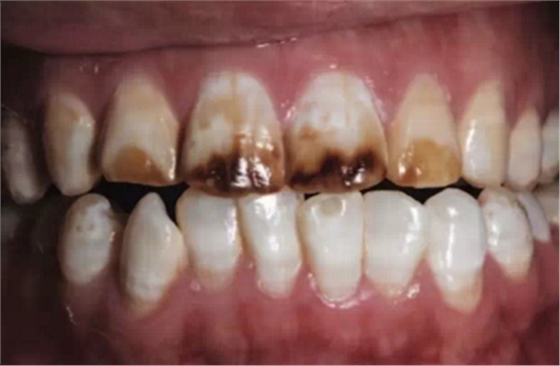

氟斑牙的臨床表現(xiàn)特點(diǎn)是在同一時(shí)期萌出的釉質(zhì)上有白堊色到褐色的斑塊,嚴(yán)重者還并發(fā)有釉質(zhì)的實(shí)質(zhì)缺損。臨床上常按其輕、中、重度而分為白堊型(輕度)、著色型(中度)和缺損型(重度)三種類型。

3.缺損型(重度):釉質(zhì)具有嚴(yán)重發(fā)育不全,常有表面形態(tài)的改變并伴廣泛著色;其顏色可自棕色至灰黑色不等。